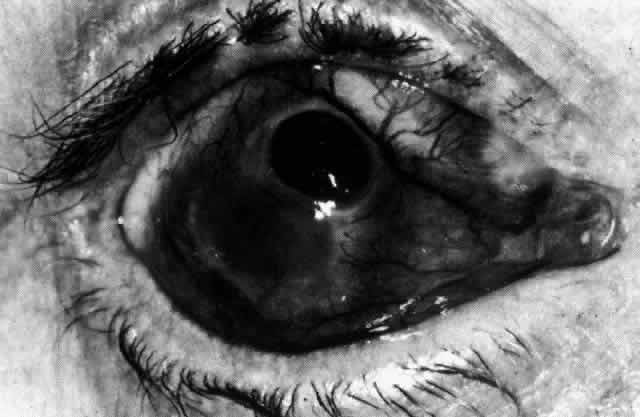

Simple and nodular episcleritis differ in their clinical courses, but in both the edema and infiltration are entirely within the episcleral tissues. The sclera is not involved. The maximum congestion is in the superficial episcleral network, with some slight congestion of the conjunctival vessels and deep episcleral vessels (Fig. 10). The intraocular structures are not involved in either variety, nor is the visual acuity affected. Anterior segment fluorescein angiography reveals a normal vascular pattern but a very rapid flow rate, with the whole transit of the dye being completed within 2 or 3 seconds (Figs. 11 and 12).

Fig. 10. Maximum congestion in the superficial vascular plexus in episcleritis. The conjunctival and deep episcleral networks are separated from the deep plexus by edema and infiltration in the episcleral tissue. (Watson PG, Hayreh S, Awdry P: Episcleritis and scleritis. Br J Ophthalmol 52(3):278–279, 1968)

The redness of simple episcleritis may be intense, varying from a fiery-red or a brick-red discoloration to a mild red flush, but it does not have the bluish tinge that is seen in scleritis. The distribution is usually sectorial but can involve the whole anterior segment of the globe. The episcleral vessels are engorged but retain their normal radial position and architecture (Figs. 13 and 14; Color Plate 1A). In simple episcleritis, there is a diffuse edema of the episcleral tissues. These tissues are sometimes infiltrated with gray deposits that appear yellow in red-free light. Surprisingly, the eye is rarely tender to the touch.

Fig. 13. Infiltration of the episclera in which the superficial episcleral vessels show maximal congestion. Conjunctival vessels are slightly congested, as is the deep episcleral plexus, whose irregular criss-cross pattern can be seen deep to the radially arranged superficial episcleral plexus.

Fig. 14. Diffuse inflammation. Superficial vessels are maximally engorged and retain their radial pattern and architecture. (See Figures 27 and 34.) (Watson PG: Connective tissue disorders and the eye. In: Recent Advances in Ophthalmology, Vol 5, pp 214–277. London, Churchill-Livingstone, 1975)